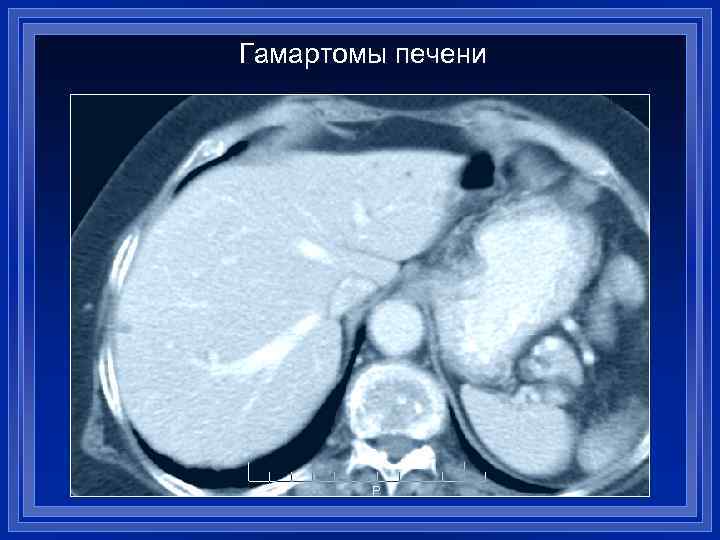

Гамартомы печени